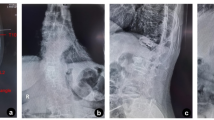

Radiological results are shown in Table 3. The histograms and Q-Q plots of CA, AVH and SI for the two groups are as follows (Supplementary Figs. 14–34). Both groups demonstrated significant improvements in CA, AVH, and SI postoperatively (p < 0.05), with no significant differences in the total correction index or correction loss between groups (p > 0.05). At 1 week postoperatively, CA was significantly higher in the OG than in the CG (7.19 ± 0.86 vs. 6.79 ± 0.97, p < 0.05). At 6 months post-implant removal, AVH was significantly lower in the OG than in the CG (89.98 ± 1.95 vs. 90.64 ± 1.33, p < 0.05). To better understand our research, we now present some radiological images from postoperative follow-up (Figs. 4 and 5).

This patient was treated with UBE technology-assisted fusion fixation. Preoperative DR Showed a severe vertebral fracture of lumbar 1 (A); The X-ray reexamination one day after the operation showed good reduction (B, C); The 6-month follow-up showed continuous callus formation (D, E); The 12-month follow-up showed that the fracture had basically healed (F, G).